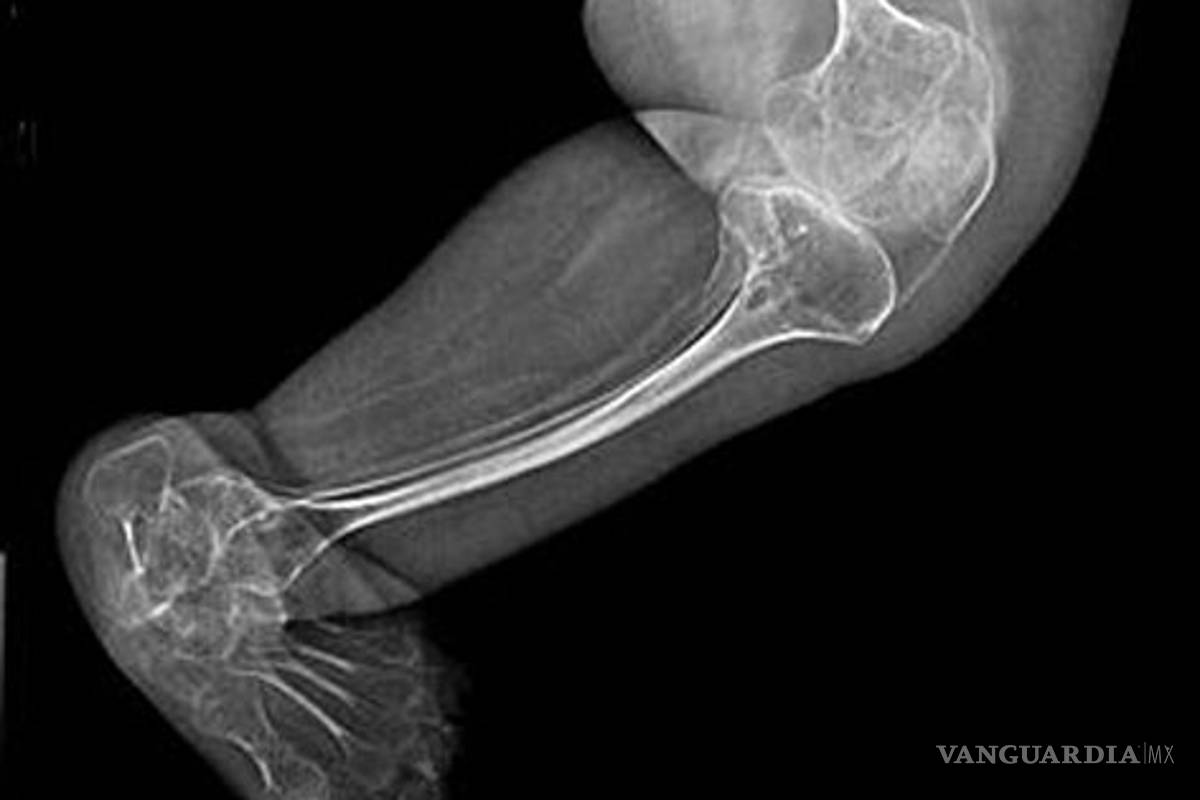

La enfermedad se caracteriza por una deficiencia en la producción de colágeno I, lo que provoca una fragilidad excesiva en los huesos

Esta enfermedad rara, comúnmente conocida como huesos de cristal, se caracteriza por una deficiencia en la producción de colágeno I, lo que provoca una fragilidad excesiva en los huesos.